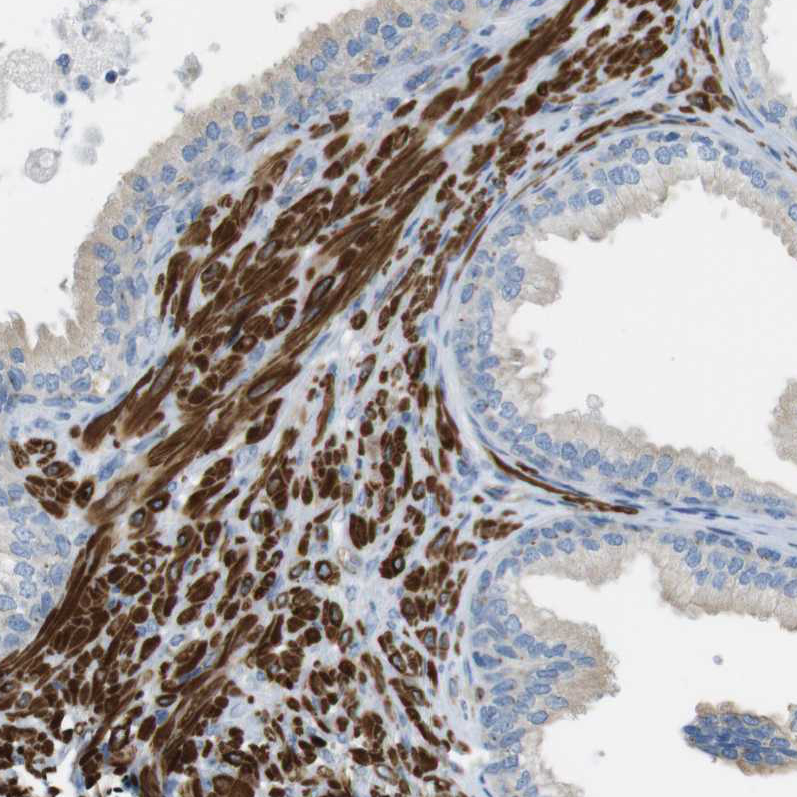

Immunohistochemical staining of human prostate shows strong cytoplasmic positivity in smooth muscle cells.